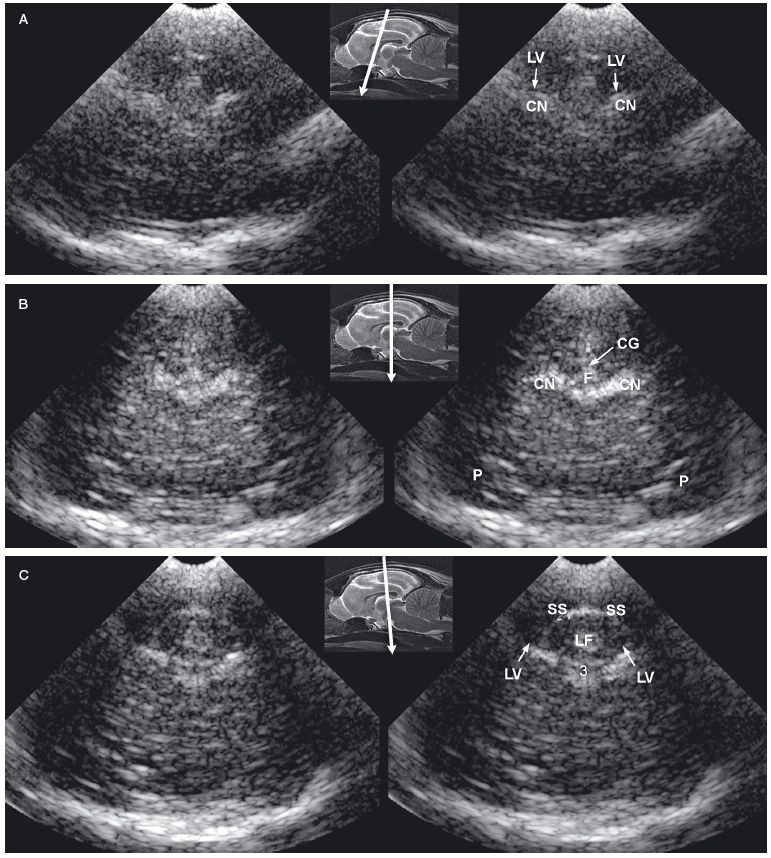

Figure 1.3. Transverse sonograms of the brain of a 1-month-old Yorkshire terrier. The ventricles are asymmetrical but within normal limits. A: Rostral sonogram. B: Sonogram at the level of the interthalamic adhesion. C: Sonogram at the level of the third ventricle. D: Sonogram with the ultrasound beam angled caudally to image the mesencephalon. E: Sonogram with the ultrasound beam angled caudally to image the cerebellum. 3, third ventricle; CC, corpus callosum; CG, cingulate gyrus; CN, caudate nucleus; F, fornix; H, hippocampus; IA, interthalamic adhesion; LF, longitudinal fissure; LLV, left lateral ventricle; M, mesencephalon; P, pyriform lobe; Po, pons; RLV, right lateral ventricle; SS, splenial sulcus; Su, subarachnoid space; T, thalamus; and V, vermis.

As the beam is swept slightly more caudally, the rostral fornix comes into view. Choroid plexus is hyperechoic while it lies on the floor of the central portion of the lateral ventricle and the roof of the temporal horn. It may be difficult to distinguish between the caudate nucleus and the adjacent choroid plexus in the lateral ventricle, so only a single hyperechoic focus might be seen on each side of the midline in some dogs. If there is sufficient CSF, the lateral ventricle can be seen.

In older puppies and adult dogs, alternating hyperechoic and hypoechoic lines represent the callosal sulcus, corpus callosum, and fornix. Comparison with histological samples suggests that the most superficial hyperechoic layer is the callosal sulcus, which contains vessels that pulsate. The corpus callosum is comprised of a hypoechoic surface with a deeper hyperechoic border. The fornix is hypoechoic. In the first few days of life, these structures may appear only as a single hyperechoic region. Detail improves as myelination progresses after birth. Most of the brain is uniformly hypoechoic, but the pyriform lobes are visible because of hyperechoic meninges dorsal to each lobe.

When the probe is tilted to sweep the ultrasound beam caudally, the dorsal portion of each hippocampus appears as a hypoechoic structure close to the midline. Dorsolateral to each of these structures, a hyperechoic area represents choroid plexus in each lateral ventricle. Another hyperechoic area is seen in the midline ventral to the level of the dorsal portions of the hippocampi. Depending on the angle of ultrasound section, this hyperechoic area may represent choroid plexus in the dorsal portion of the third ventricle or pia mater that is located more caudally in the adjacent subarachnoid space. Vessels and trabeculae in the subarachnoid space may create a complex of echoes that outline the mesencephalon and cause it to appear as a dome-shaped hypoechoic structure. The petrous temporal bones will create irregular hyperechoic echoes on the floor of the cranium on each side of the midline deep to the hypoechoic pyriform lobes.

More caudally, the osseous tentorium is a hyperechoic structure shaped like an inverted V. In older animals, this structure often prevents visualization of the caudal brain, but the medulla and cerebellum can be imaged in neonatal animals. The medulla is hypoechoic. The vermis of the cerebellum is represented by a stack of hyperechoic lines seen in the midline. Each lateral cerebellar hemisphere is located more laterally as a hypoechoic structure.